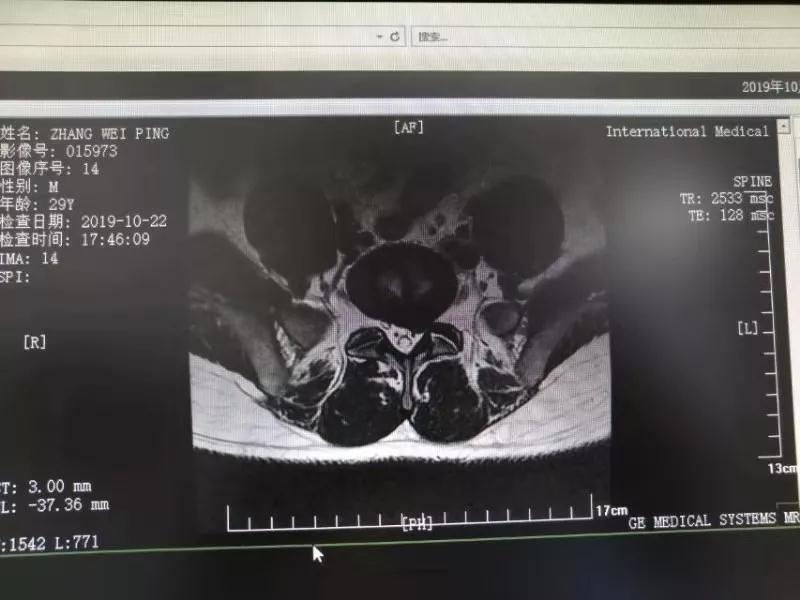

10月25日,29歲的患者小張了解到西安國際醫(yī)學(xué)中心骨科醫(yī)院專家云集,一大早便在家人的陪同下,來到西安國際醫(yī)學(xué)中心骨科醫(yī)院就診。“我腰痛持續(xù)2年多,最近感冒后腰痛癥狀明顯加重了。”小張面露苦楚,因?yàn)殚L期腰痛、左下肢放射性疼痛,她晚上睡覺不能平躺,經(jīng)常疼得睡不著,需要口服止痛藥物才能有所緩解。走路走不了多遠(yuǎn)就開始腿抽的疼,嚴(yán)重影響到工作和生活。

結(jié)合患者的檢查以及年齡情況,王自立副院長推薦讓專門研究椎間孔鏡技術(shù)王雄勛主任給小張做微創(chuàng)的椎間孔鏡手術(shù)。該手術(shù)創(chuàng)傷很小,不影響脊柱的穩(wěn)定性,尤其適合于椎間盤突出的年輕患者,懷著對(duì)骨科醫(yī)院專家的信任,小張與家人商議后,接受手術(shù)治療。